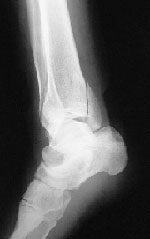

X線所見:正面像で脛骨下端部の骨折が認められ、末梢骨片は後外方へ転位していた。中枢骨片側面像では前下方への転位を認めた。腓骨は下端部で斜骨折を確認したが、転位は認めなかった

(図1)。

レントゲン側面像。

脛骨下端部に骨折線を認める。 |

レントゲン正面像。

腓骨下端部に骨折線を認める。 |